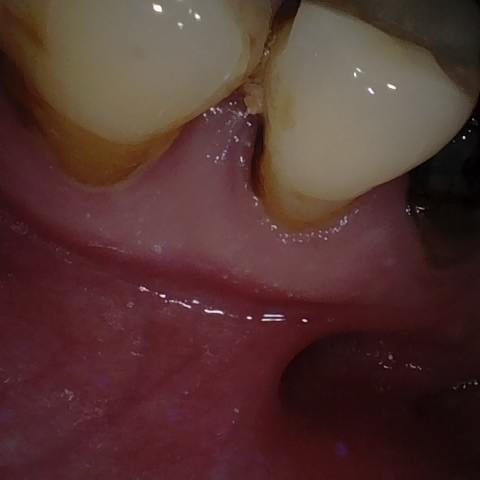

Annotated as "Good"